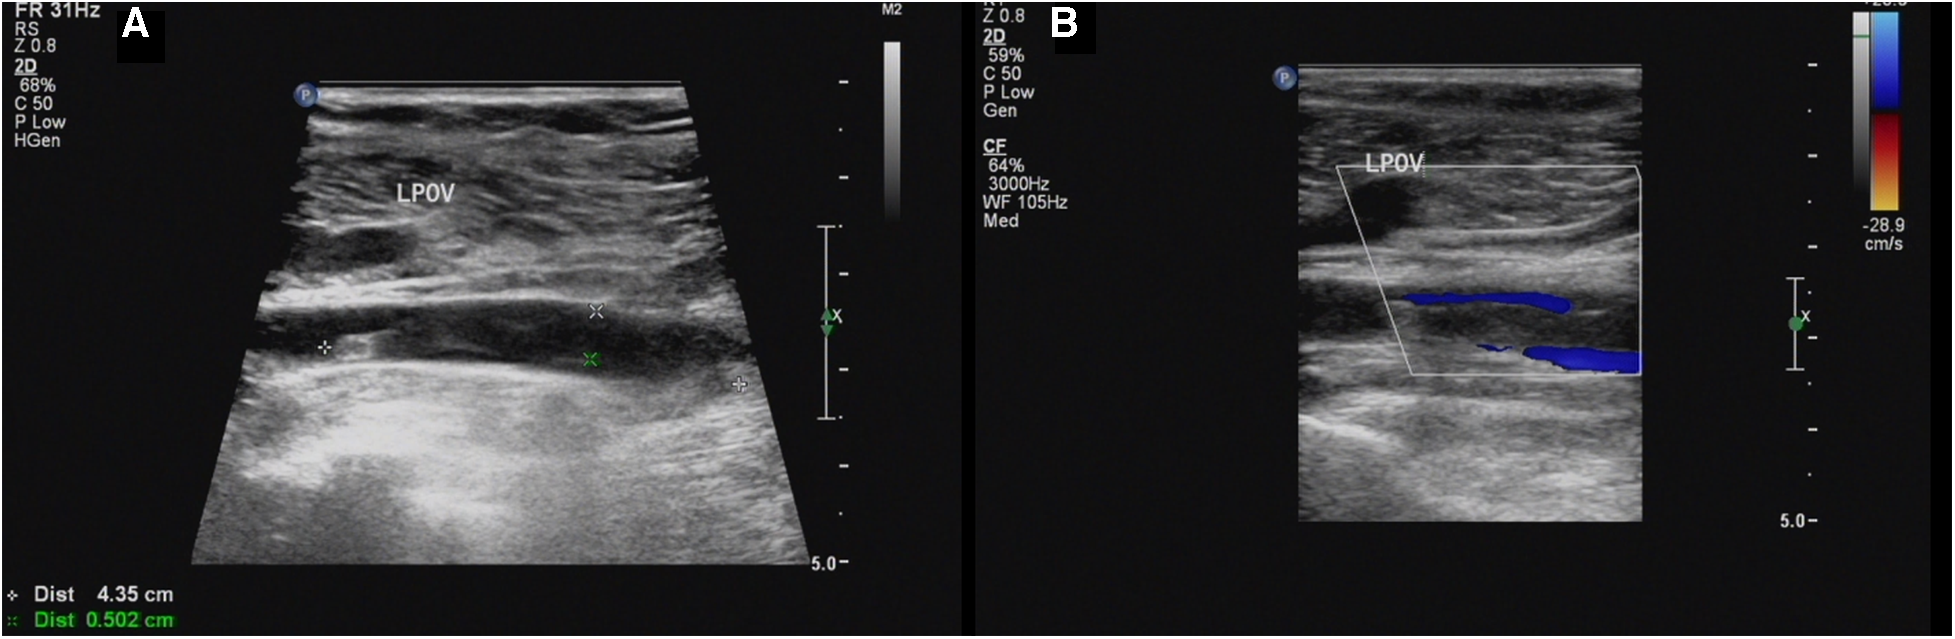

Our ultrasound showed left lower extremity deep vein thrombosis (DVT), including a thrombus in the popliteal vein measuring approximately 43.5mm × 5.0 mm (Figure 1). Electromyography revealed no neurogenic or myogenic injury in either lower limb. Computed tomography pulmonary angiography (CTPA) showed no signs of thrombosis in the pulmonary artery and severe stenosis of the proximal lumen of the abdominal trunk.

Figure 1

(A,B) Sagittal sonogram and sagittal color Doppler US limb of thrombosis of the left popliteal vein (LPOV).